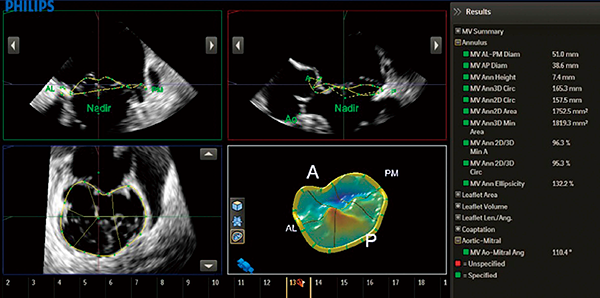

MVNは,3D計測時の断面設定の際,ガイド画面が表示され,ガイドに画像を合わせて設定した後,弁輪部にポイントを設定すれば,弁輪面積など多くの計測と弁のシェーマを表示することができるツールである(図5)。

図5 僧帽弁解析ソフトMVNA.I.